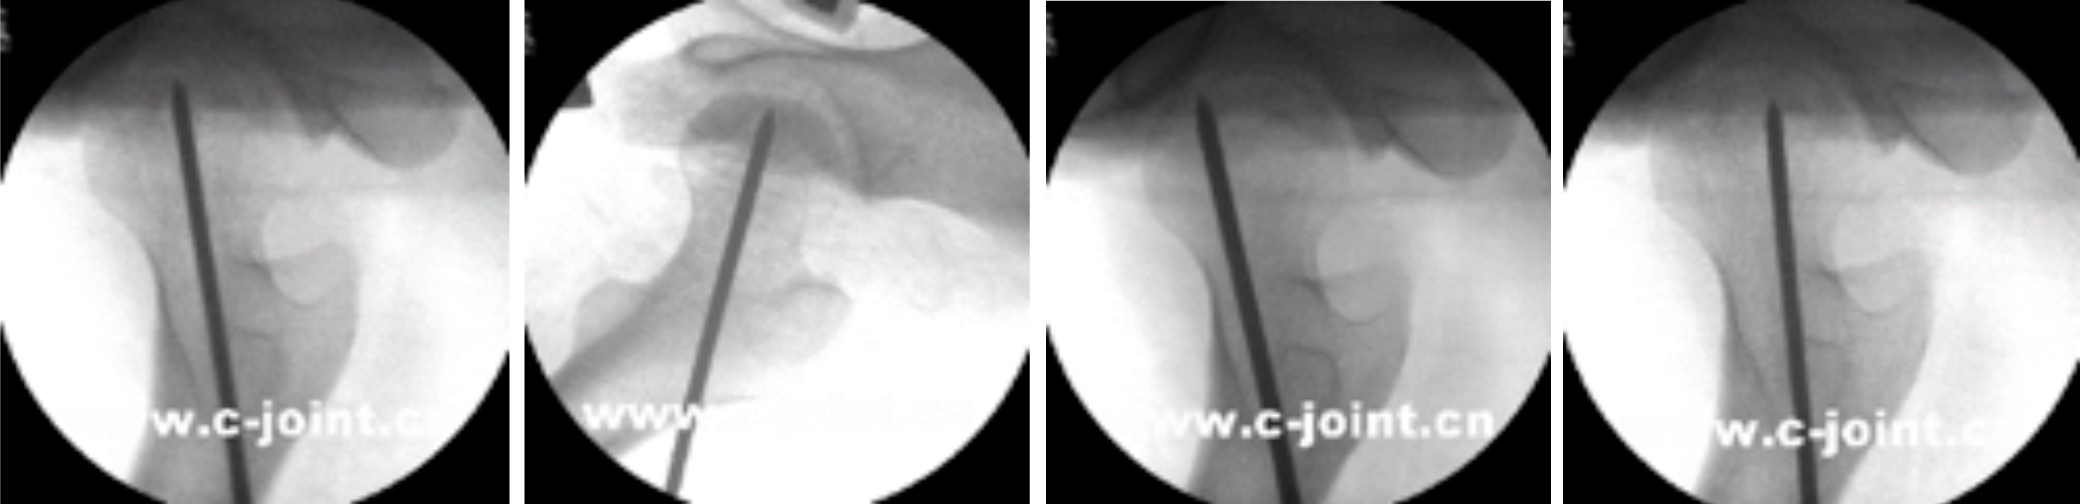

3、手足骨折的微创治疗:

手足部位的骨折,好发于青壮年劳动力,传统治疗方法采用切开复位钢板螺钉内固定,由于对软组织剥离大,神经血管损伤及术后肌腱粘连发生率高,造成术后手指活动不良甚至致残;且需要二次手术取出钢板螺钉,给患者恢复带来困难。而北京清华长庚医院创伤骨科中心应用独有的髓内针治疗该类骨折,做到了“不切开”——仅留一针眼,“不出血”——术中出血约1ml,术后功能康复效果良好。

第五掌骨骨折闭合复位髓内针治疗前后对比图,该手术仅通过一个针眼完成固定,实现“不切开”“不出血”的微创治疗。